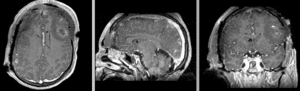

Registration Results

unregistered exam 1 & 2

Exam 2 aligned to Exam 1 (affine only)

Exam 2 aligned to Exam 1 (affine+BSpline)

BSpline deformation only of Exam 2